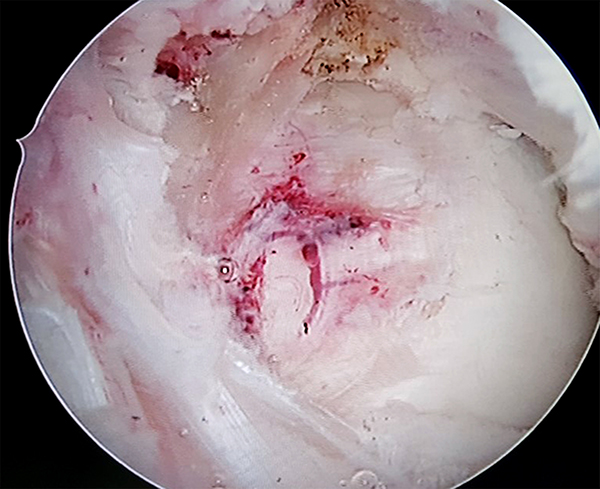

El paciente fue derivado al equipo de artroscopia de rodilla para evaluar la resección artroscópica de la misma. Se realizaron tres portales. El portal AL y AM estándar con objetivo el desbridamiento periférico en región anterior con preservación marginal. El portal PM con el objeto del desbridamiento periférico posterior y la exéresis en bloque de la pieza, lo cual se logro sin dificultad ni necesidad de realizar artrotomía (figs. 3, 4 y 5).

Figuras 3, 4 y 5: Superior derecha e izquierda: Se observa visión artroscópica por portal anterolateral y posteromedial, localización retro LCP. Inferior: Visualización artroscópica posterior a exéresis completa.